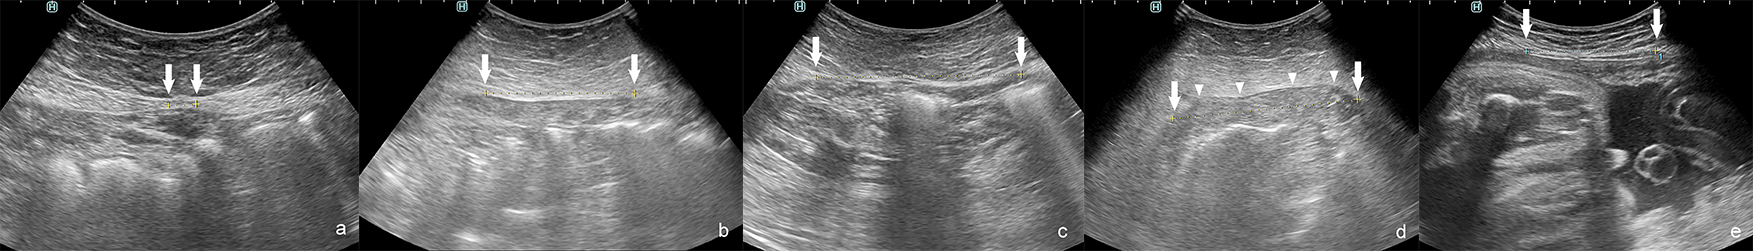

Fig. 1.Diastasis recti abdominis (DRA) in relaxed state. (a) During curl up. (b) Arrows–medial margins of rectus muscles; arrowheads–costal arches.

Fig. 3.Interrecti distance (IRD) measured by ultrasonography: correct IRD 8 mm. (a) Examples of diastasis recti abdominis (DRA). (b–e) IRD 66 mm. (b) IRD 74 mm. (c) IRD 82 mm during curl up. (d) IRD 52 mm in pregnant woman. (e) Arrows–medial margins of rectus muscles, arrowheads–protruded linea alba during curl up.